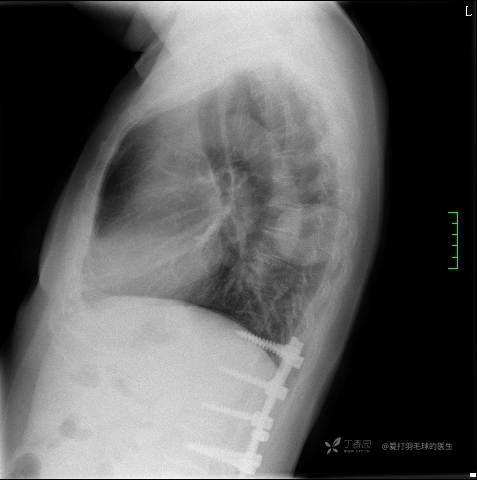

中年女性,全身多处“疙瘩”,长了切,切了又长,分型是关键,已公布结果。

患者性别:女

患者年龄:44岁

主诉:患者因反复右侧腰痛伴右下肢麻木2年余入院。

简要病史:自诉右甲状腺功能亢进症多年,规律服药,平素多有心悸、胸闷、活动后明显。既往腰椎椎管内肿瘤切除术。